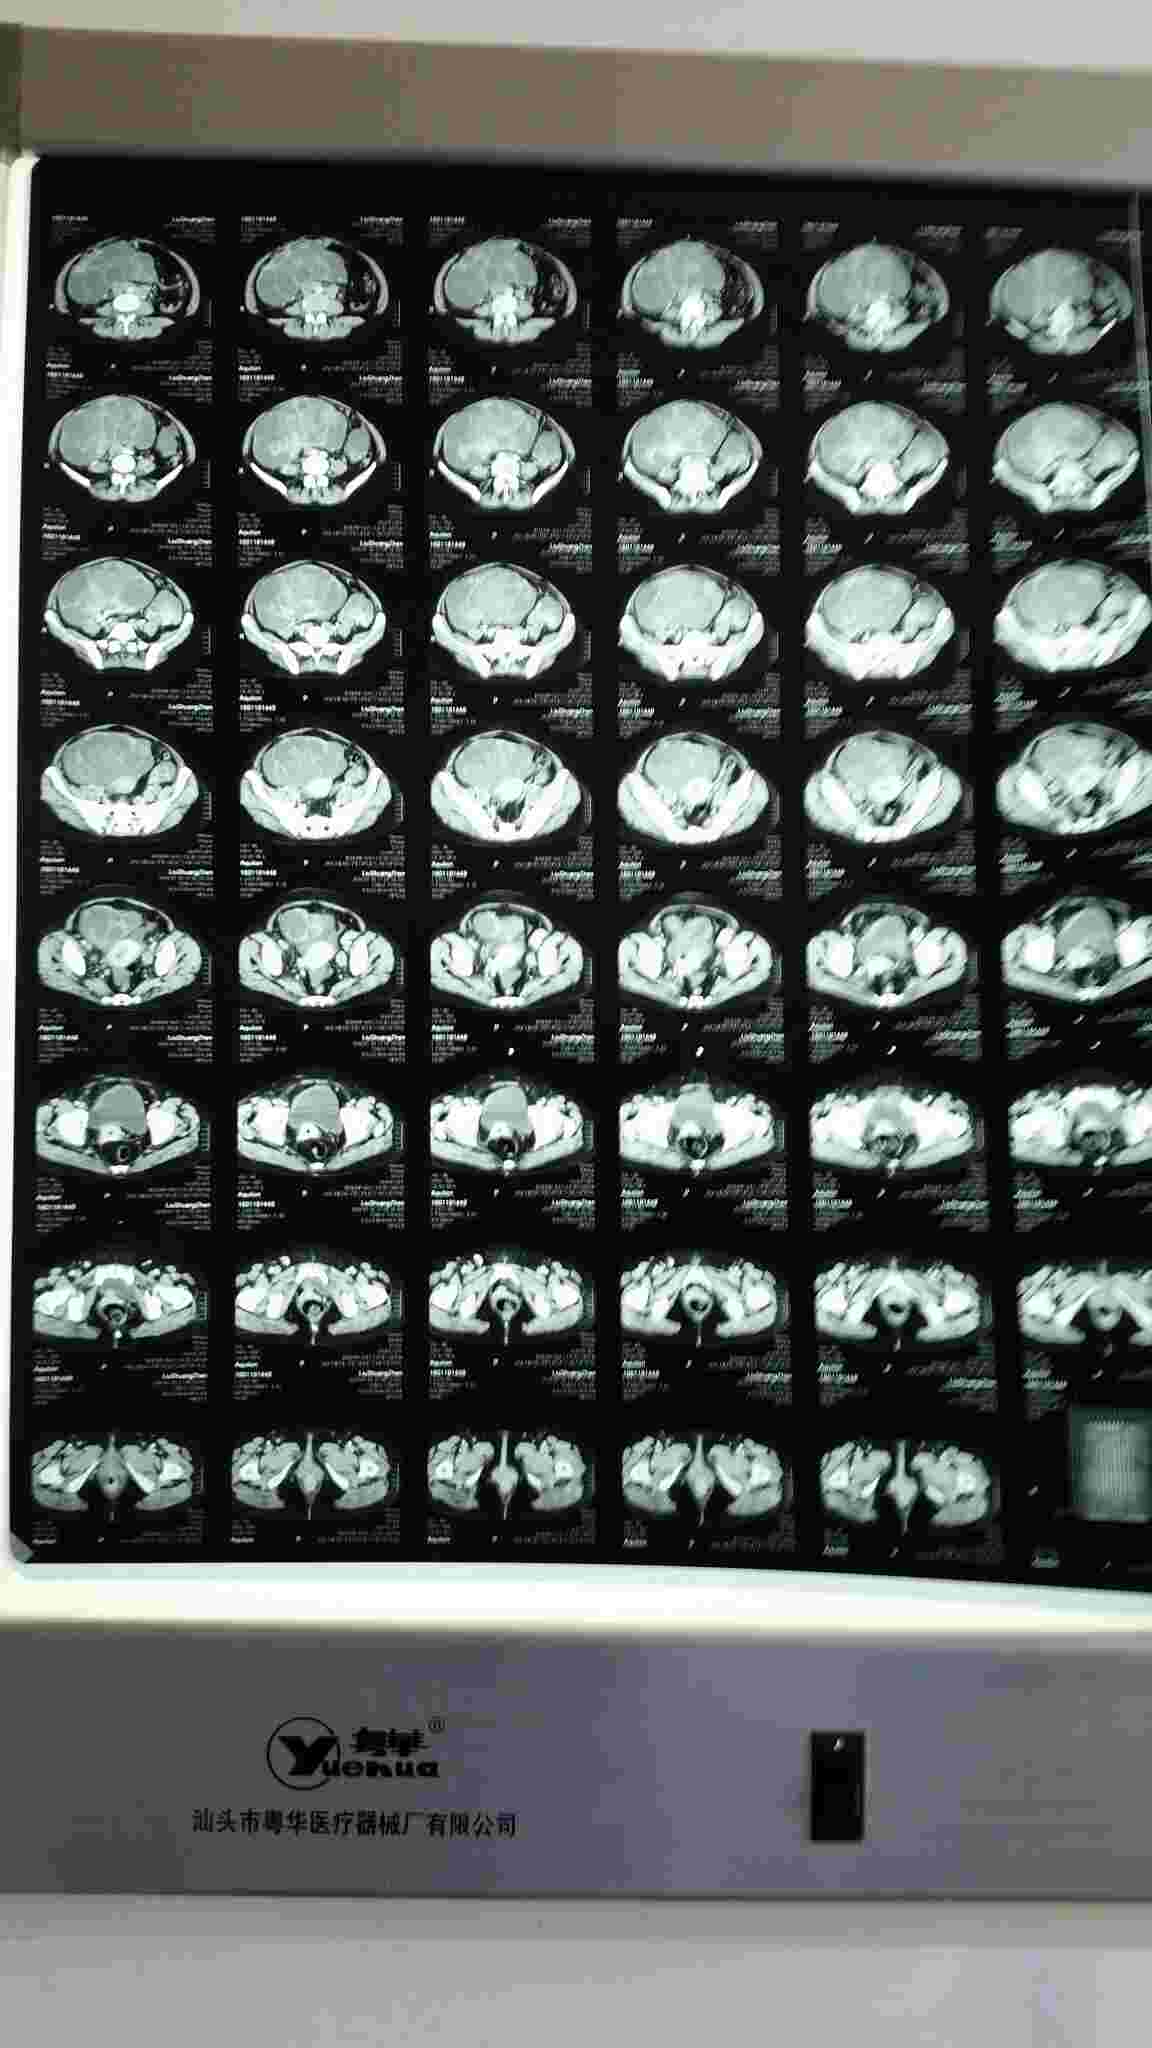

女,52岁,发现宫颈癌一年余,气短、胸闷半天入院。胸腹部增强扫描如下图,目前心率115-140次/分左右,血压120_170/80_110mmhg,呼吸25一32次/分,血氧饱和度77一85。給予吸氧、心电监测、抗感染、平喘、化痰治疗,大家看有什么好办法